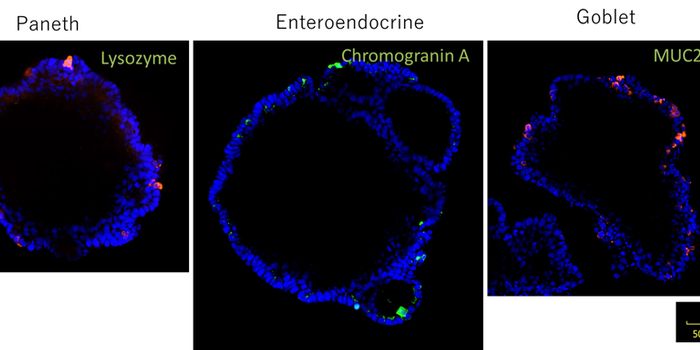

MAR 21, 2021Cell & Molecular BiologyScientists now have a new way to investigate the processes underlying human development, diseases that may arise during ...